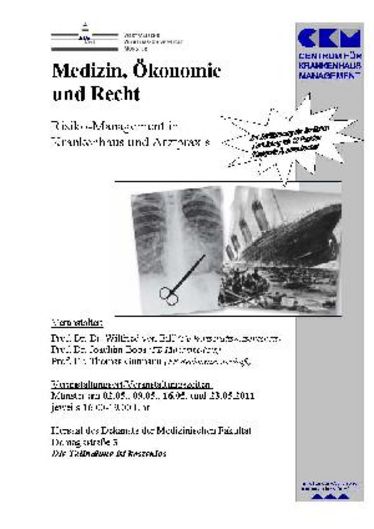

02.05.2011

SFB492-Kolloquium: Mechanisms that regulate diapedesis of leukocytes through the endothelial barrier

SFB492-Kolloquium: Mechanisms that regulate diapedesis of leukocytes through the endothelial barrier